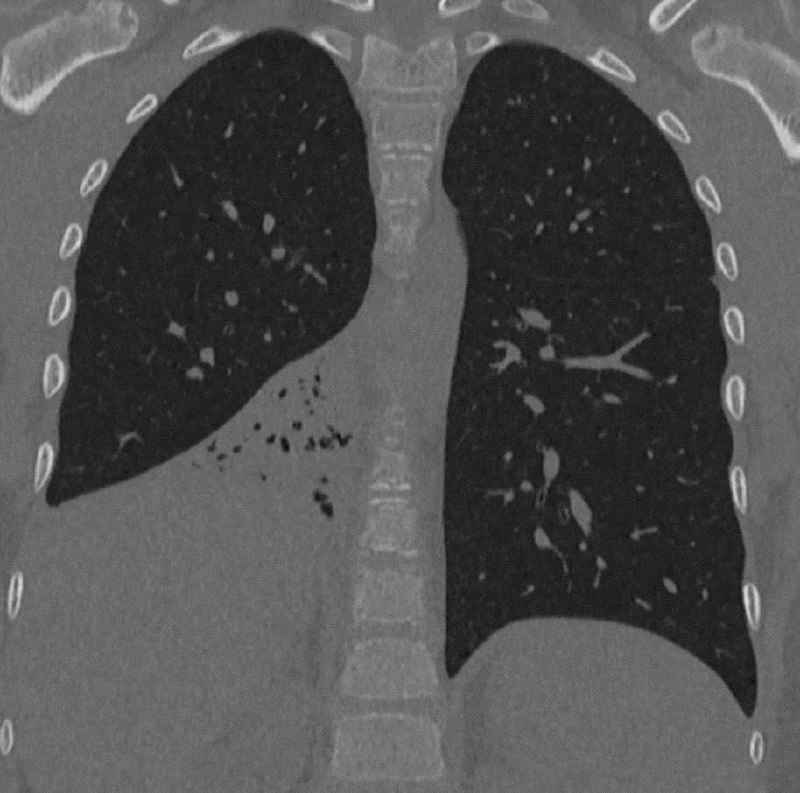

Пластиковый колпачок полгода скрывался в бронхах ребенка. Восьмилетний мальчик в течение шести месяцев страдал от повторяющихся пневмоний и постоянно болел. Врачи Центра Рошаля выяснили, что в бронхах школьника застрял пластиковый колпачок, из-за которого было воспалено правое легкое и нарушена его работа. После удаления инородного предмета пациент пошел на поправку. ⭕ Подписаться | Прислать новость | Буст

Пластиковый колпачок полгода скрывался в бронхах ребенка.

Восьмилетний мальчик в течение шести месяцев страдал от повторяющихся пневмоний и постоянно болел. Врачи Центра Рошаля выяснили, что в бронхах школьника застрял пластиковый колпачок, из-за которого было воспалено правое легкое и нарушена его работа. После удаления инородного предмета пациент пошел на поправку.